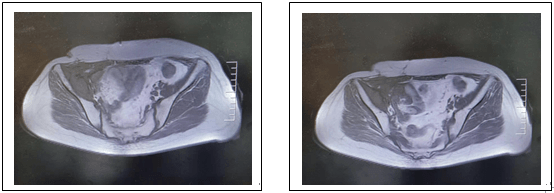

下圖為放療前病變及放療靶區